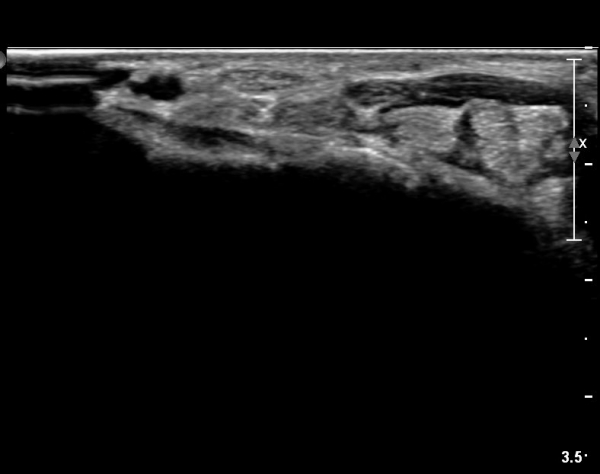

ÇÏŰ½ºÆ½(°íÁÖÆÄ) ŽÃËÀÚ¸¦·Î °üÂûµÈ ¸ð½À¿¡¼­ Á¤Áß½Å°æ ºÎºÐ ½Å°æ´Ù¹ßÀÇ Àú¿¡ÄÚ

º¯È­°¡ ¶Ñ·ÈÇÔ(»çÁø 6, 7).

Á¤Á߽Űæ Á¾´Ü¸é°Ë»ç¿¡¼­µµ ¼Õ¸ñ ¸»´ÜºÎ¿¡¼­ ¼ö±Ù°ü ±ÙÀ§ºÎ±îÁö À̾îÁø Àú¿¡ÄÚ

Á¾¾çÀÌ °üÂûµÊ(»çÁø 8, 9, 10, 11).